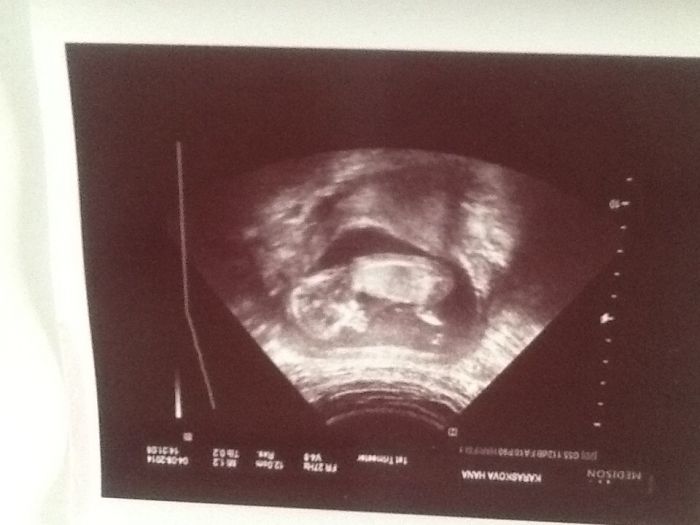

Ahojky těhulky tak jsem naprosto nadšená.Miminko si celou dobu cumlalo palec a dr.se to povedlo zachytit na foto :-).Jsme dlouháni od zadečku k hlavičce má 7cm a s nožičkama celkem 11cm.Veškeré vady či roštěpy vyloučeny a krevní testy prý nemohly dopadnout lépe.Moč.měchýř plný :-).Prostě vše jak má být.Dcera se ptala úplně na všechno :-),co je to černé okolo miminka kde ma ručičky nožičky atd..tak teď je chytrá jak rádio.14.8.nás čeká poradna a tripltesty.Přikládam foto

Hani to je krásné,dr. může být profi fotografWink  to jste opravdu velicí my měli jen 62mm celkovou nevím